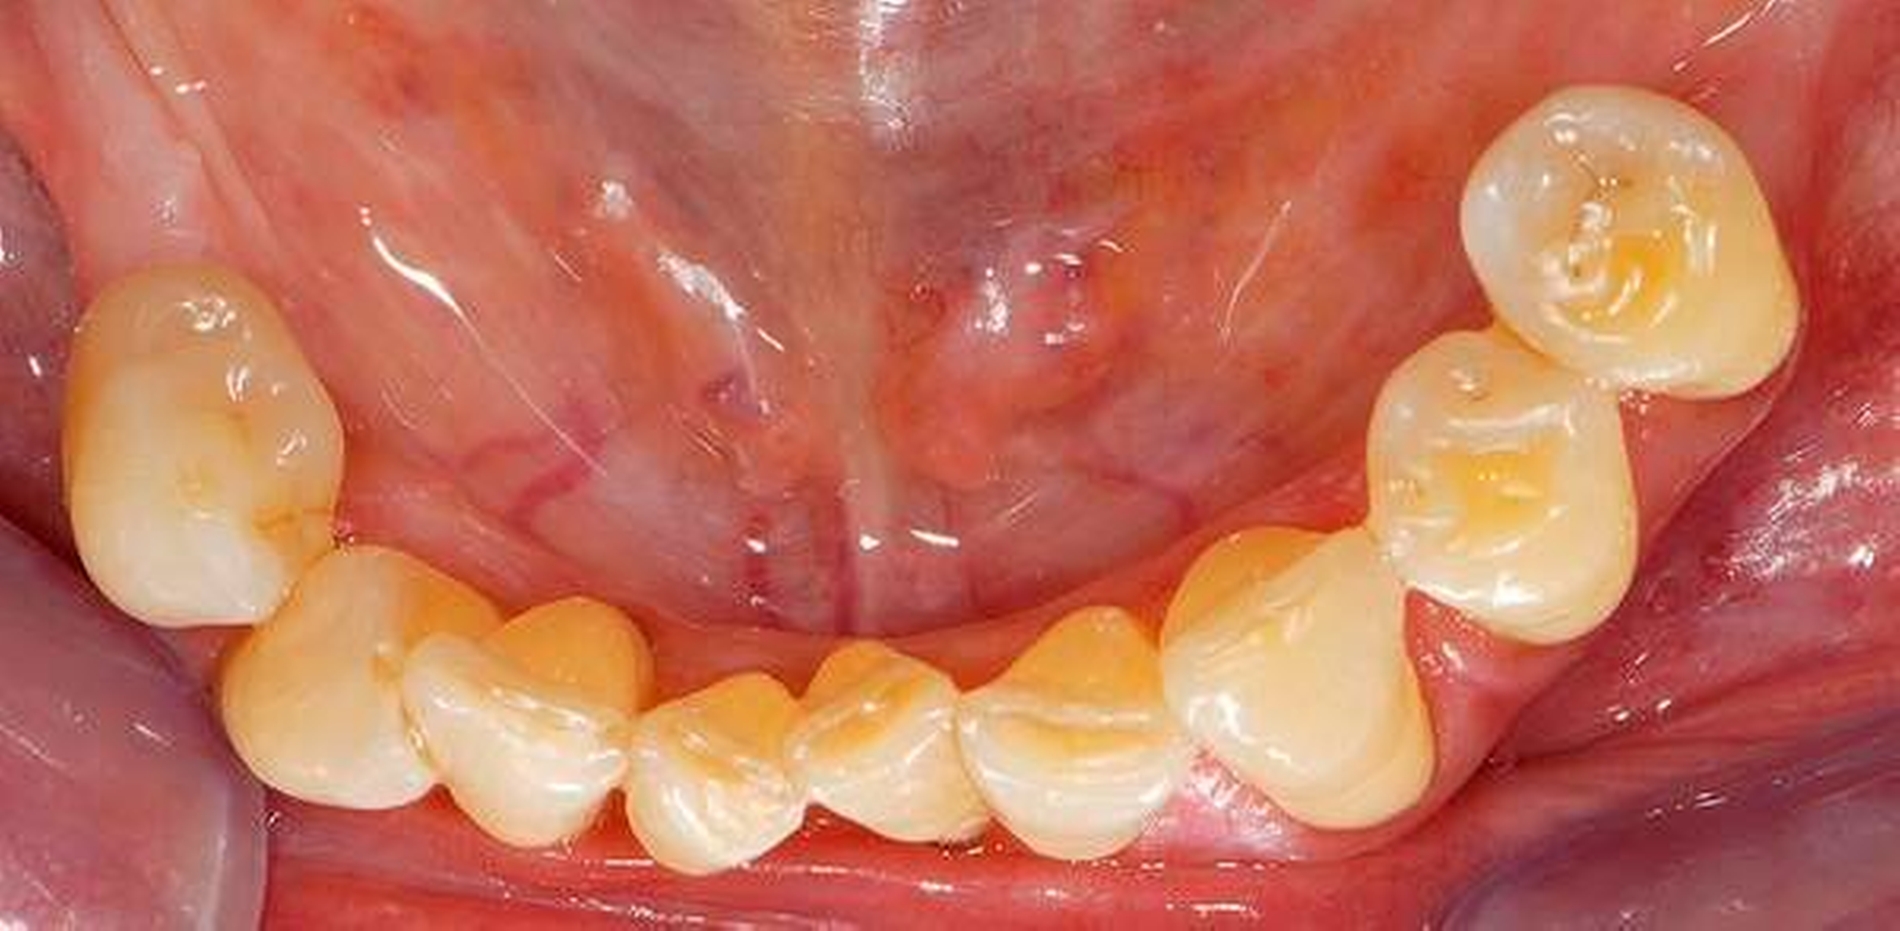

Wenn beispielsweise ein Patient mit tiefen Zahnfleischtaschen Interdentalraumbürsten anwendet, die ohne nennenswerten Widerstand die Zahnzwischenräume passieren, kann man nicht erwarten, dass ihm dies zu einem großen Nutzen für die Zahngesundheit verhilft. Dies betrifft auch Implantatträger [Staehle et al., 2016]. In Abbildung 7 ist ein Patient gezeigt, der trotz Parodontalbehandlung und regelmäßiger Reinigung mit einer – zu dünnen – Interdentalraumbürste hohe Sondierungstiefen und Bluten nach Sondieren aufwies. Erst nach Umstellung auf eine größere Interdentalraumbürste mit längeren Seitenborsten und einem genügend hohen Passagewiderstand durch den Interdentalraum wurde der Taschenfundus mit den Borsten besser erreicht und es kam zu einem deutlichen Entzündungsrückgang.

Eine zahnmedizinisch sinnvolle frugale Intervention für viele Menschen wäre, ihnen eine Handzahnbürste zu empfehlen und dies bedarfsgerecht durch geeignete Interdentalraumbürsten zu ergänzen. Dies wäre in manchen Fällen wesentlich besser, als jemanden durch die alleinige Empfehlung einer elektrischen Hightech-Zahnbürste in einer falschen Sicherheit zu belassen und auf Interdentalraumbürsten zu verzichten. Allerdings muss man einräumen, dass derzeit Interdentalraumbürsten relativ teuer und verschleißanfällig sind und dass das oft sehr unübersichtliche und unvollständige Produktangebot nicht den tatsächlichen Erfordernissen genügt. Insofern besteht hier auch von Herstellerseite Handlungsbedarf.